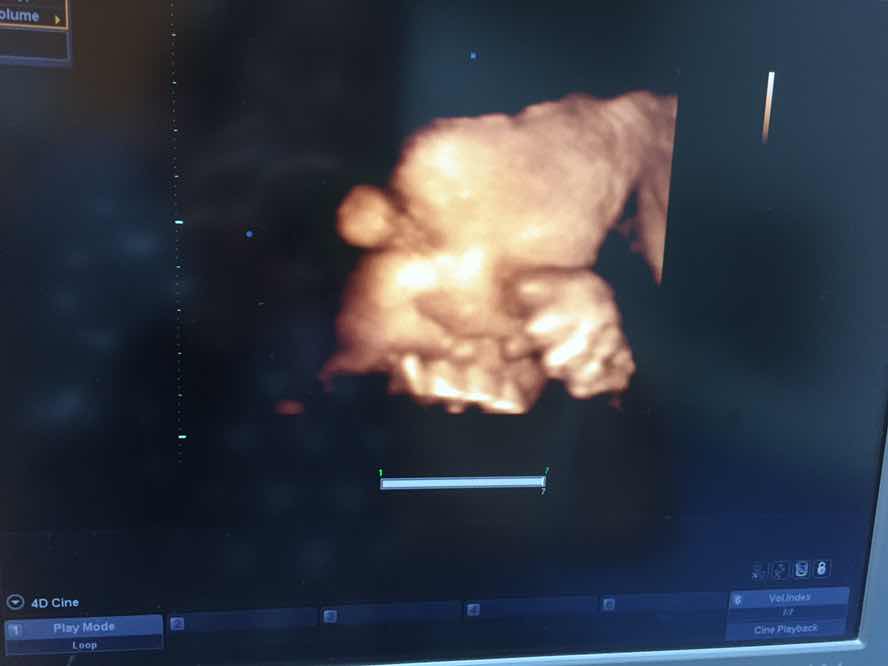

ผู้หญิงค่ะ